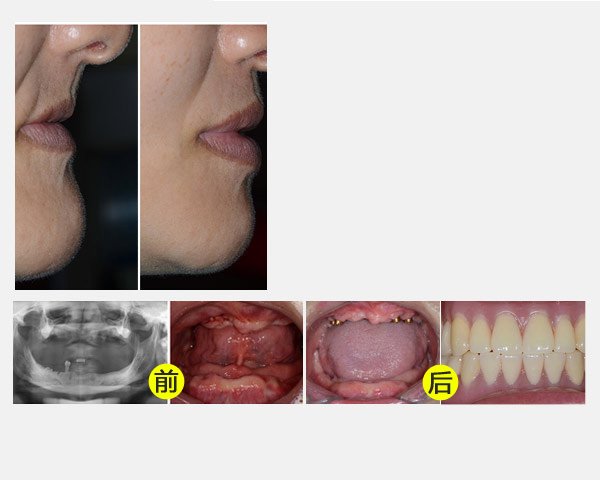

全口牙缺失种植修复案例